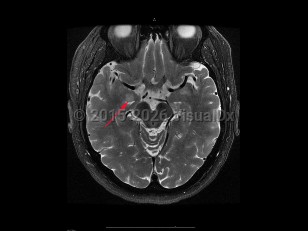

To distinguish encephalitis from other causes of encephalopathy, core components of the presentation of encephalitis include the presence of fever (within 72 hours before or after presentation), cerebrospinal fluid (CSF) pleocytosis (≥ 5 /mm3), or MRI or electroencephalogram (EEG) changes consistent with encephalitis.